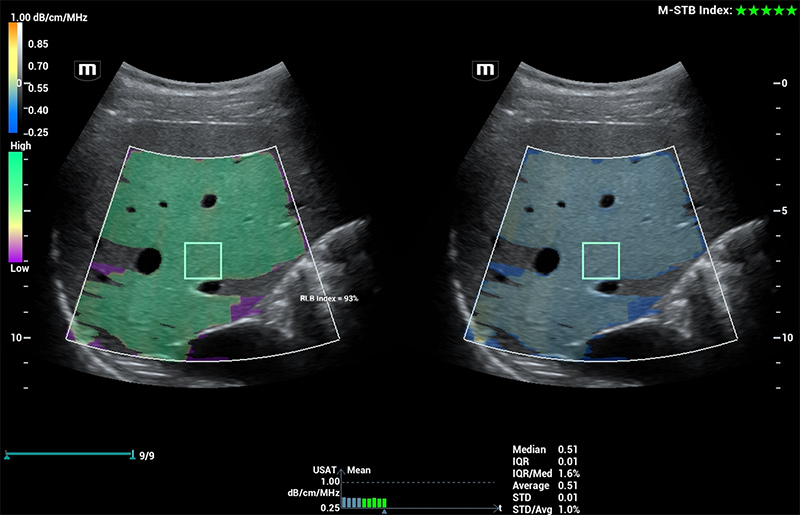

Com tecnologia ZST+

A plataformaZST+ representa um salto extraordinĂĄrio na tecnologia de ultrassom, passando da tradicional forma??o de feixe para o processamento de dados de canal. Essa inova??o revolucionĂĄria supera as compensa??es tradicionais entre resolu??o espacial, resolu??o temporal e uniformidade do tecido, resultando em uma qualidade de imagem inigualĂĄvel com infinitas solu??es de gera??o de imagens.

O Resona I9 fornece solu??es clĂnicas abrangentes para aplica??es dedicadas. Com base em percep??es aprofundadas em diferentes cenĂĄrios clĂnicos, ele oferece inova??es que fornecem aos usuĂĄrios extrema clareza, inteligĂȘncia excepcional e confian?a excepcional no diagnĂłstico.